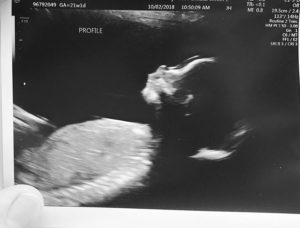

We conceived so quickly, and despite big obstacles, our baby boy is doing VERY well. He’s growing on target, heart, weight and anatomy look perfect. We’re feeling him move all the time.

Currently I am 21 weeks. What an amazing blessing! Thanks again, so much!